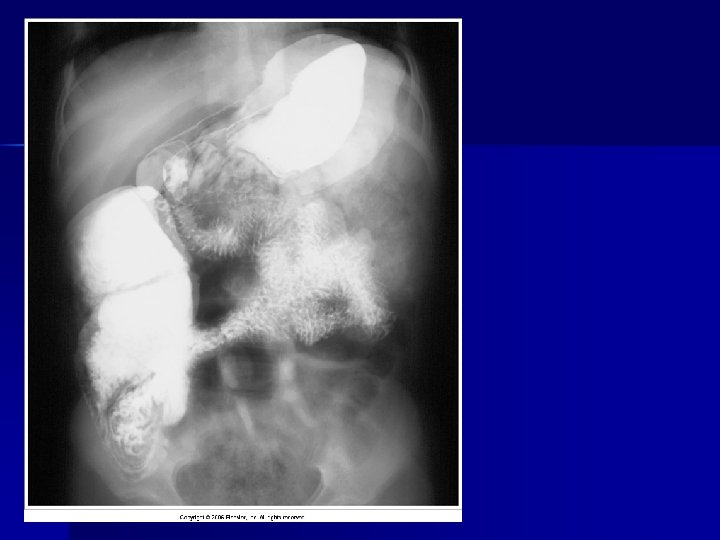

Artifact

Evaluating Images What do you think?

n n n Does this show good detail? Is all of the anatomy present? How is the density / contrast?